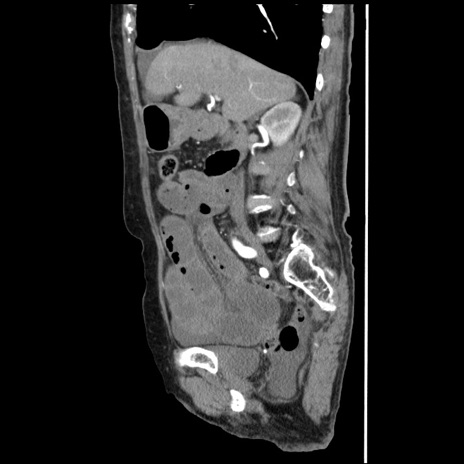

横断像

冠状断像

【症例】80歳代女性

【主訴】腹痛

【現病歴】8時間前から腹痛あり来院。

【既往歴】糖尿病、脂質異常症、子宮体癌にて子宮全摘術

【身体所見】意識清明・会話良好だが腹痛で苦悶様、全腹部にわたって反跳痛と圧痛あり

【データ】WBC 13600、CRP 0.14、LDH 224、CK 90